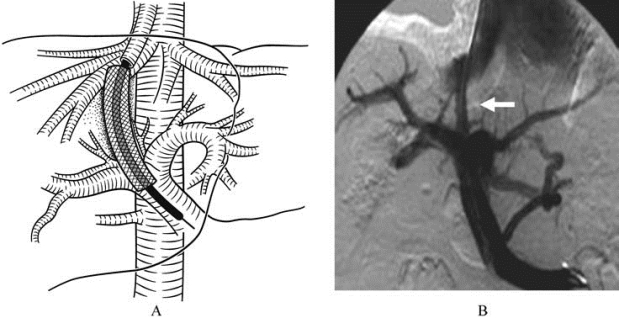

是最具代表性的综合性介入治疗技术。TIPSS集穿刺术、血管成形术、支架置入术等多项介入技术于一体,用于治疗肝硬化门静脉高压症。